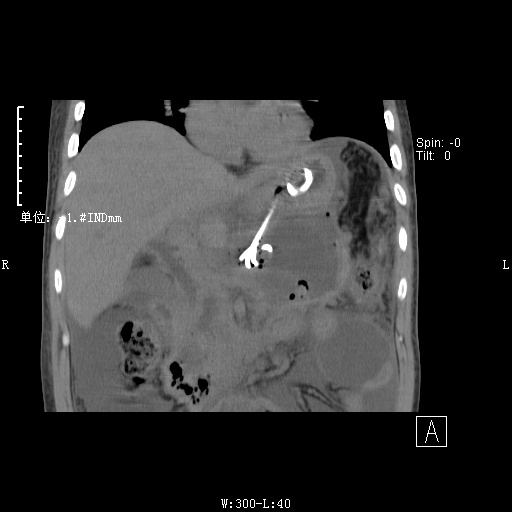

经过充分的术前准备,在麻醉科、介入室的配合下,3月11日由陈达凡主任及消化内科团队为患者实施了超声内镜引导下胰腺巨大假性囊肿支架置入引流术。手术中,首先通过超声内镜寻及胰腺假性囊肿,发现病灶多处局部血供丰富,如操作不慎,即有发生大出血的可能。针对此情况,超声内镜正可发挥优势,其多普勒显示功能对血流具有敏锐探查能力,在它引导下避开血管,选择了最佳的引流部位。在穿刺针进入囊腔后,应用专门电切装置,依次切开胃壁、囊腔壁,并进行瘘管扩张,可见大量囊液流出。为保证囊液的流出持续通畅,置入了双支架进行引流。整个手术过程创伤小,基本没有出血,且在全麻状态下施行操作,患者没有痛苦感受,术后第二天便可做床边一般活动及逐渐恢复饮食。

患者病程较长、病情复杂,且遵义市五医之前未开展过此类手术,为保证操作的顺利进行,消化内科同仁反复多次进行术前讨论,针对术中和术后的各个环节、可能出现的意外做了充分准备,同时和上一医南院的李百文主任、罗声政博士、龚晓媛护士长密切商讨,制定了严密的手术方案。并请相关科室进行会诊,在术前麻醉评估中,麻醉科闫明主任认为患者假性囊肿巨大,必须注意预防大量囊液流入胃内后反流导致的误吸,操作应在气管插管全麻下进行,以保证手术安全。